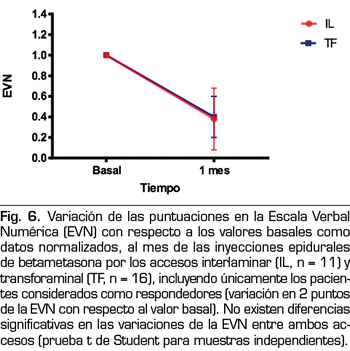

Cuando se compararon los cambios en la EVN y en el Índice de Interferencia de aquellos pacientes cuyas respuestas se consideraron satisfactorias utilizando betametasona por vía interlaminar o parasagital (11 y 16 respectivamente), no se observaron diferencias en ninguno de estos parámetros (Figuras 6 y 7).

La puntuación en la EVN de los pacientes tratados con betametasona por vía interlaminar cambió de 8,4 ± 1,4 a 3,2 ± 3, lo que equivale a un 61 % de mejoría, mientras que el Índice de Interferencia cambió de 6,5 ± 2,2 a 4,5 ± 2, lo que equivale a un 30 % de mejoría. En el caso de la betametasona administrada por vía transforaminal, la EVN pasó de 8,7 ± 1,1 a 3,3 ± 2,3, lo que equivale a un 63 % de mejoría, mientras que el Índice de Interferencia pasó de 7,13 ± 2,1 a 4,75 ± 3,1, lo que equivale a un 33 % de mejoría.

La Figura 6 muestra los cambios observados en la intensidad del dolor en los pacientes que presentaron respuestas satisfactorias en ambos grupos, expresados como porcentaje de cambio. En ambos grupos los pacientes pasaron de padecer un dolor intenso a uno leve. Por lo tanto, tomando por separado al grupo de “respondedores”, el dolor pasó de intensidad elevada a leve en ambos grupos, con una mejoría de 2 puntos en cuanto a la repercusión funcional del dolor medido con el Índice de Interferencia (Figura 7). No se observaron diferencias estadísticamente significativas en los resultados obtenidos comparando ambos accesos cuando se toman por separado los pacientes con respuestas positivas.